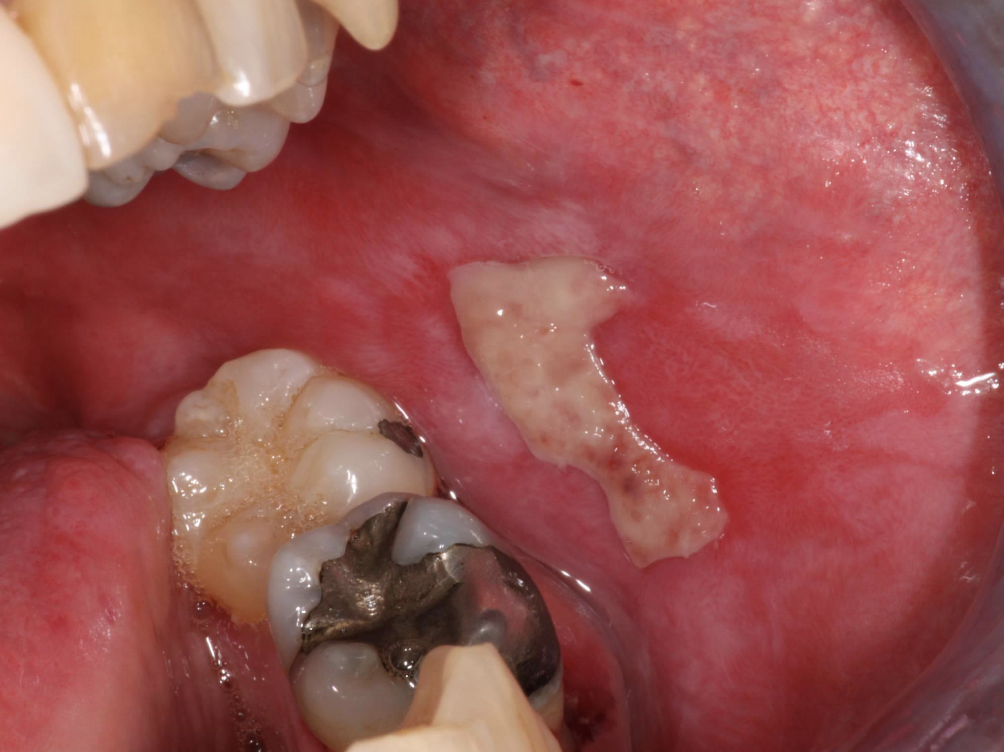

what condition?

• Least common form

• Usually symptomatic

• Ulcers with striae and erythema

ulcerative lichen planus